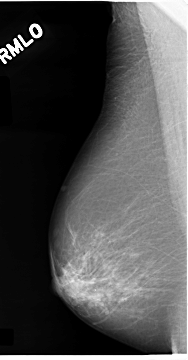

C_0074_1.RIGHT_MLO

RIGHT_MLO LINES 4672 PIXELS_PER_LINE 2432 BITS_PER_PIXEL 12 RESOLUTION 50 NON_OVERLAY